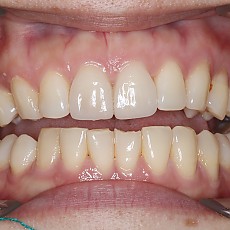

시술전후사진 6 페이지

Total 189건 6 페이지